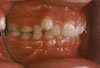

ORTA HAT UYUMSUZLUĞU

Üst orta hat ile alt orta hat uyumsuzdur. Arka bölgede kapanış bozukluğu mevcuttur. Fonksiyon ve estetik etkilenebilir.